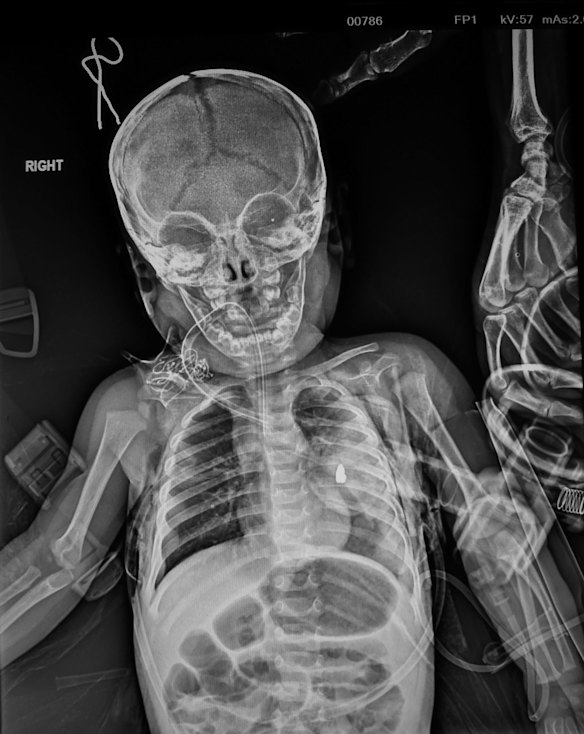

The X-ray of 11-month-old Qasid Radhwan showing the piece of shrapnel in his chest. It caused a part of his lung to collapse.Credit:Kate Geraghty